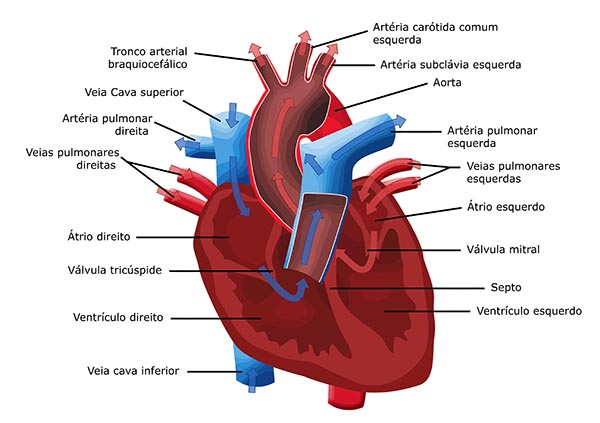

Órgãos do Sistema Cardiovascular

Os órgãos do sistema cardiovascular garantem a circulação do sangue pelo organismo e, consequentemente, o transporte de oxigênio e nutrientes para todas as células.

Coração

O coração é um órgão muscular oco formado pelo tecido muscular cardíaco. É responsável pelo bombeamento do sangue para todo o corpo por meio de contrações rítmicas involuntárias (sístole e diástole).

Vasos sanguíneos

Os vasos sanguíneos, são os canais por onde circulam o sangue pelo corpo, sendo eles:

- Artérias: responsáveis pelo transporte do sangue do coração para os tecidos;

- Veias: responsáveis pelo transporte do sangue dos tecidos para o coração;

- Capilares: vasos bastante delgados e que apresentam paredes finas, ou seja, permite a troca de substâncias entre o sangue e os tecidos.